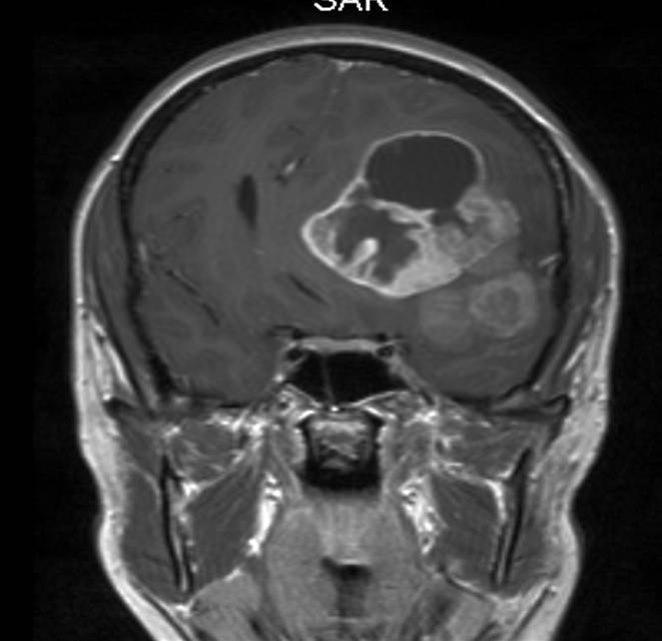

Anaplastisk ependymom, koronalt snitt

Gjengitt med tillatelse av Radiologisk avdeling, Universitetssykehuset Nord-Norge